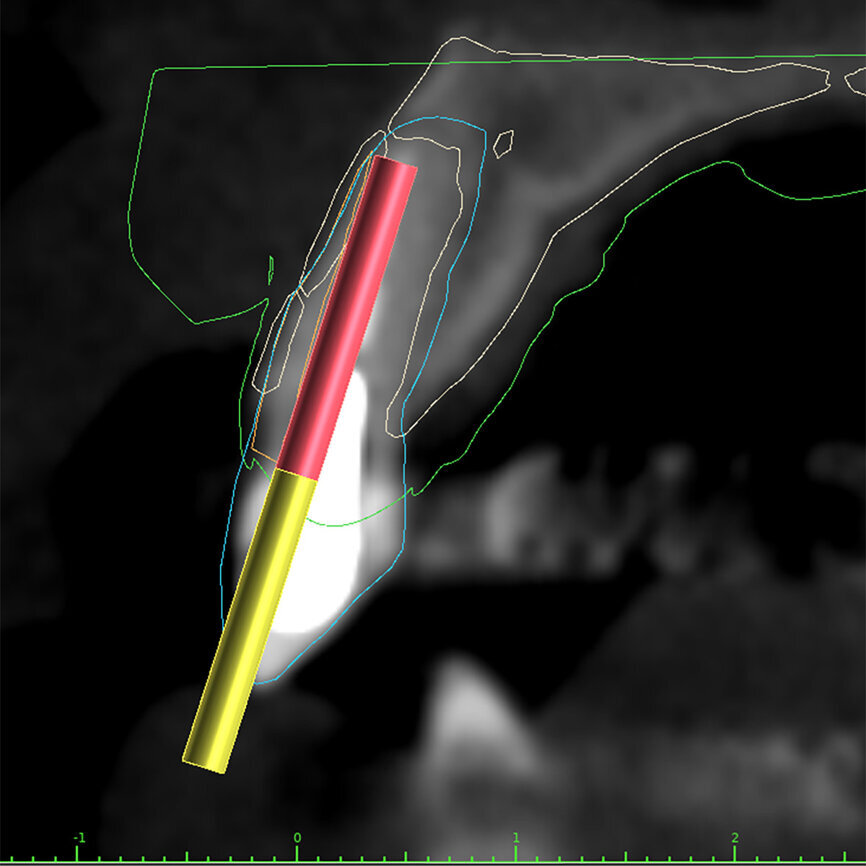

Fig. 3a: Planning the initial drill path using a custom implant design (red) to match the

diameter of the initial drill to reach the tooth apex. The abutment projection is shown in yellow.

Fig. 14b: Using the native Carestream 3D Imaging Software,

a simulated implant (red outline) and abutment projection (yellow outline) was positioned within the available bone to avoid the root fragment.

One indication for PET is when a patient presents with a horizontally fractured clinical crown (Fig. 1). While a 2D radiograph will reveal the extent of the horizontal fracture, length of the remaining root and approximation of the bone apical to the root, there is not enough information to plan for a PET procedure. A CBCT scan is recommended in order to fully appreciate the root position within the alveolus and the potential difference between the trajectory of the bone and the trajectory of the root as can be visualised with a cross-sectional image (Fig. 2). Utilising interactive treatment planning software makes it possible to plan the initial drill path to accurately section the root to its apex (Fig. 3a). This can be accomplished by creating a custom implant design to match the diameter of the initial drill with an abutment projection in order to fully appreciate the trajectory through the clinical crown (Blue Sky Plan, Blue Sky Bio). It is important to visualise the root fragment that will remain in order to properly simulate the position of the implant in the alveolus (Fig. 3b). The apical portion of the implant can be positioned to gain stability in host bone using the Triangle of Bone. It is important to note that a cross-sectional slice may only be 0.125 mm in thickness based on the CBCT acquisition, and therefore all images in all views must be visualised to confirm the plan. Utilising 3D segmentation (separating objects by density values), it is possible to define each root and further assess the simulated position of the implant with a sagittal cut through the 3D reconstructed volume (Fig. 4).

Case report

A 62-year-old male patient presented with a hopeless prognosis for a post fracture in the left central incisor requiring extraction (Figs. 12a & b). The preoperative periapical radiograph revealed an existing implant supporting a metal–ceramic restoration for the adjacent region #11 (Fig. 13). The CBCT (CS 9600, Carestream Dental) cross-sectional image revealed a favourable preoperative condition relating to the trajectory of the endodontically treated root to the alveolus for a PET procedure (Fig. 14a). Using the native Carestream 3D Imaging software, a simulated implant and abutment projection was positioned within the available bone to avoid the root fragment (Fig. 14b).